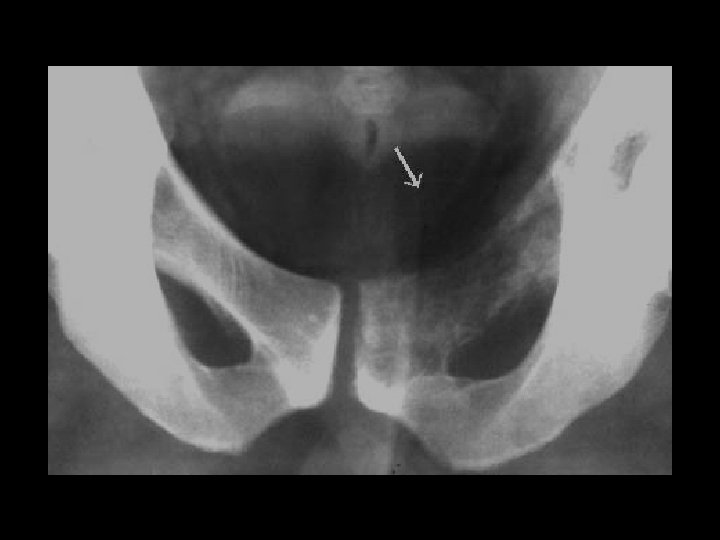

Malignant fibrous histiocytoma • Findings: – Permeative lesion of the superior pubic ramus • ddx: – Lymphoma – Multiple myeloma – Metastasis – Osteomyelitis